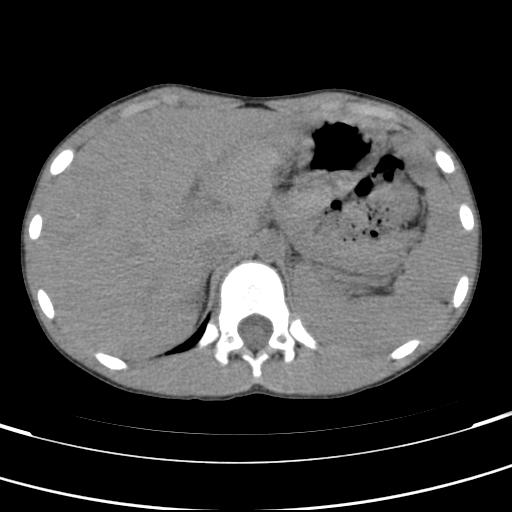

标题: PED3157:左肾缺如,请教脾脏的改变?、、

男孩,9岁。胃部不适。

脾脏位于左侧,但数个脾脏呈分离状态,左肾缺如,右肾代偿肥大。考虑多脾综合征。